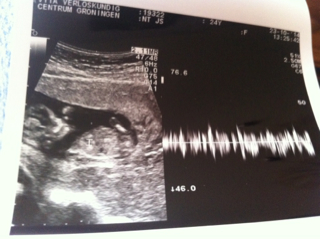

12 weeks 3 days.. Any one like to take a guess?? Nub

IF that is a nub I see, I'm going to lean girl (60/40) but really hard to tell. Congrats!

Girl lean here!:)

Leaning boy.

I think girl

girl

Girl lean but a bit ealryy

Leaning boy

Possible boy lean x

Opinion are divided I see haha. Have to wait till November 7th to find out! I'm so hoping for a boy :$ but ill be happy if it's a girl too..